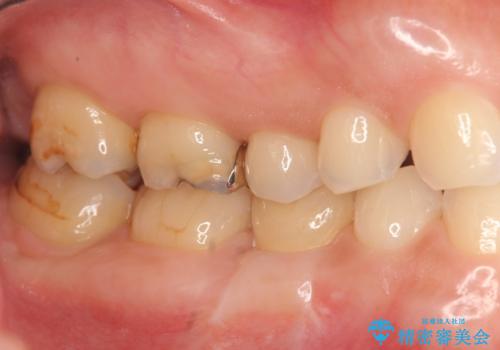

- 大人になっても残っていた乳歯が噛むと痛くなり、治療を求めて来院されました。

残す手段を検討しましたが大きな虫歯・根尖病変の存在し、大きく歯ぐきも腫れ炎症も強く認められる状態を改善するため抜歯を行いインプラントによる咬合機能回復を計画します。

大人になっても残っている乳歯は根管治療や他の治療で残せる場合もありますが、今回のように状態が悪い場合早期に抜歯をすることで歯槽骨が温存でき十分に安定した骨量でインプラントによる機能回復を達成することができました。